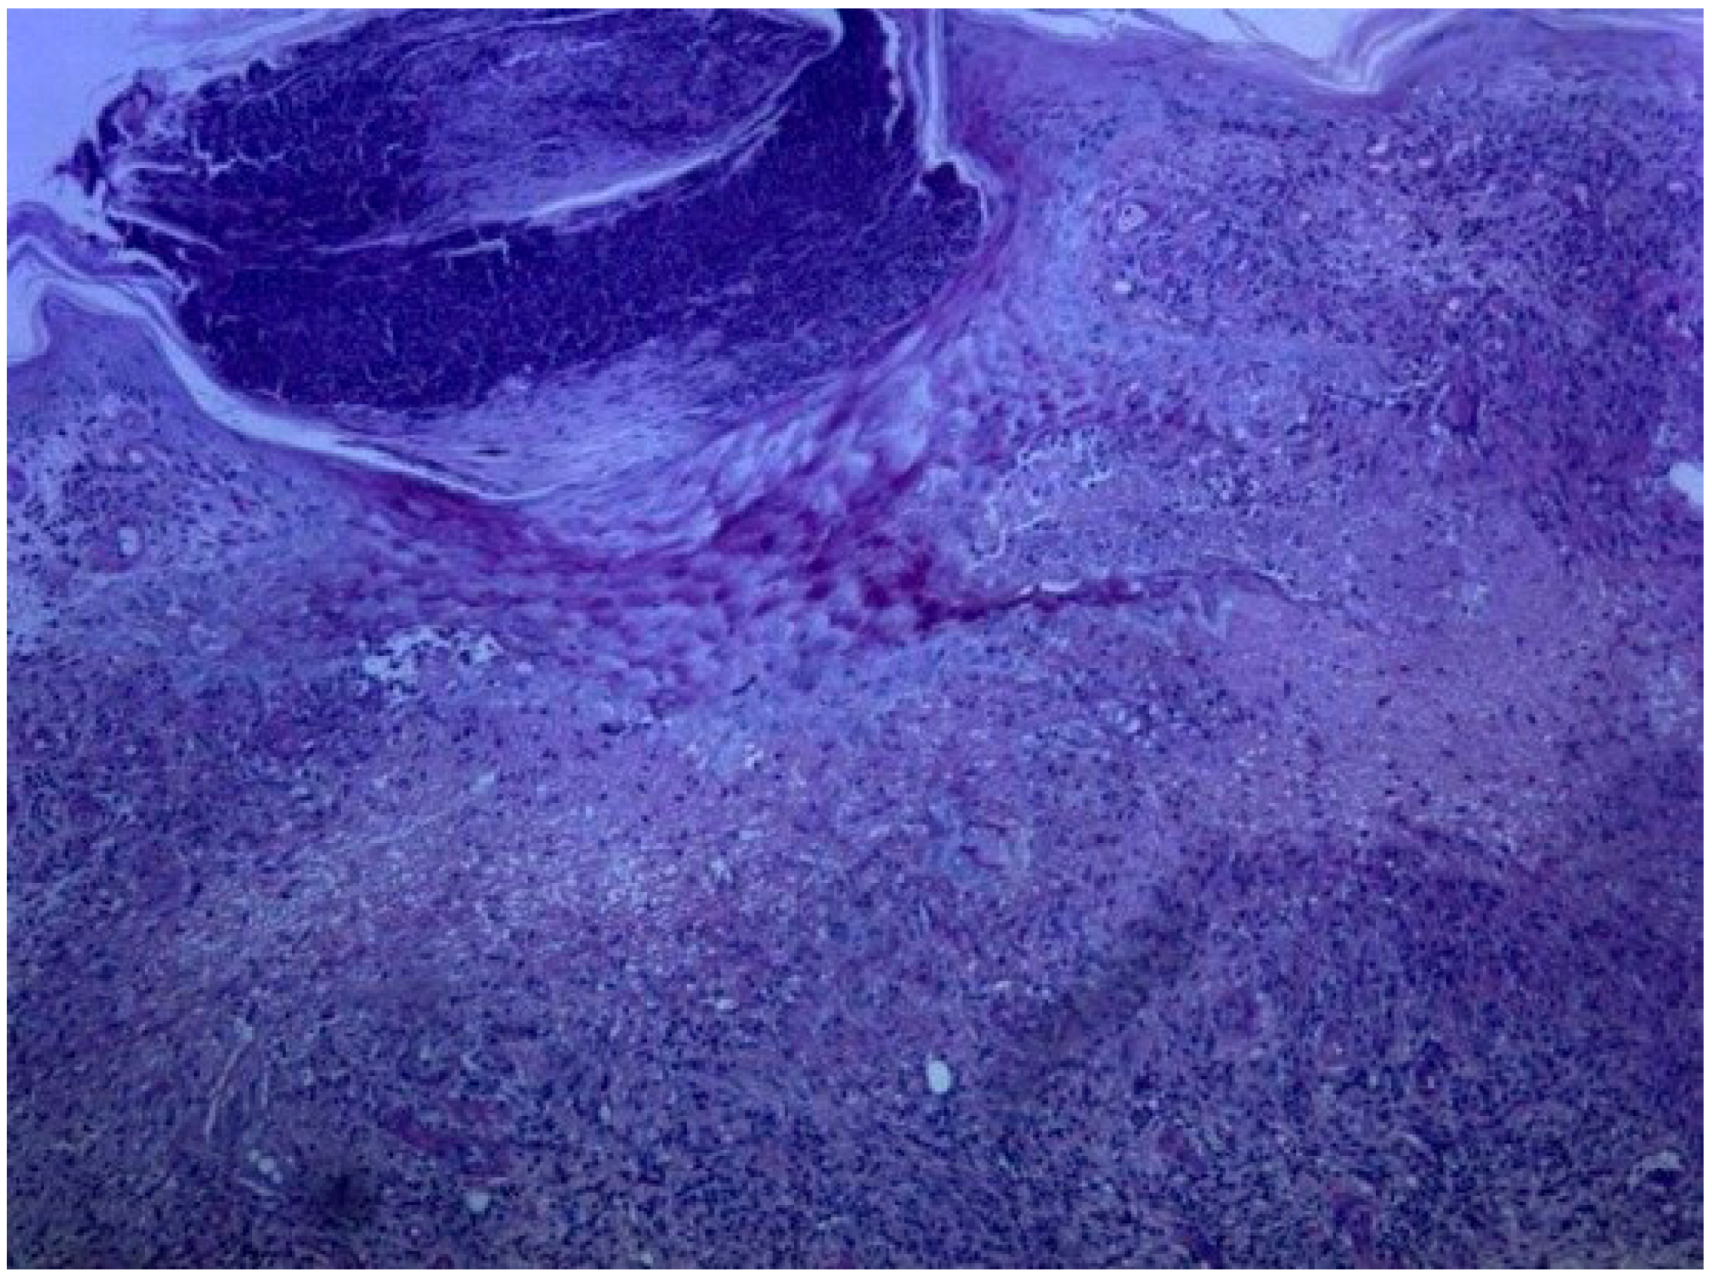

A 72 year-old women was referred to our department due to a 3-month history of a post-traumatic and slightly pruritic erythematous and exudative plaque located on her left leg. She had already been treated with several antibiotics without any clinical improvement. The patient also complained of recurrent gelatinous material extruding from the central area of the plaque. She denied any prior skin conditions or relevant medical history and had no history of recent travel. On physical examination it was observed on the anterolateral lower third of the left leg, a rounded, ill-defined erythematous plaque with 3 cm long axis, centered by small erosion covered by adherent crust (Figure 1). Around the plaque there were some discrete erythematous papules. The differential diagnosis included mycobacterial infection, subcutaneous mycosis, perforating dermatoses, pyoderma and squamous cell carcinoma. A punch biopsy was performed and the histological examination revealed a well-defined nodular infiltrate occupying the papilar and reticular dermis mainly composed of lymphocytes and histiocytes. Collagen degeneration with transepithelial elimination and multiple palisading granulomas surrounding the necrobiotic collagen were prominent (Figure 2 and Figure 3). The exposed features were highly suggestive of perforating granuloma annulare. The patient was treated with betamethasone dipropionate cream applied once daily and a complete resolution of the lesion was observed in three weeks (Figure 4).

Figure 3.

Collagen degeneration and transepidermal elimination (H&E × 100).